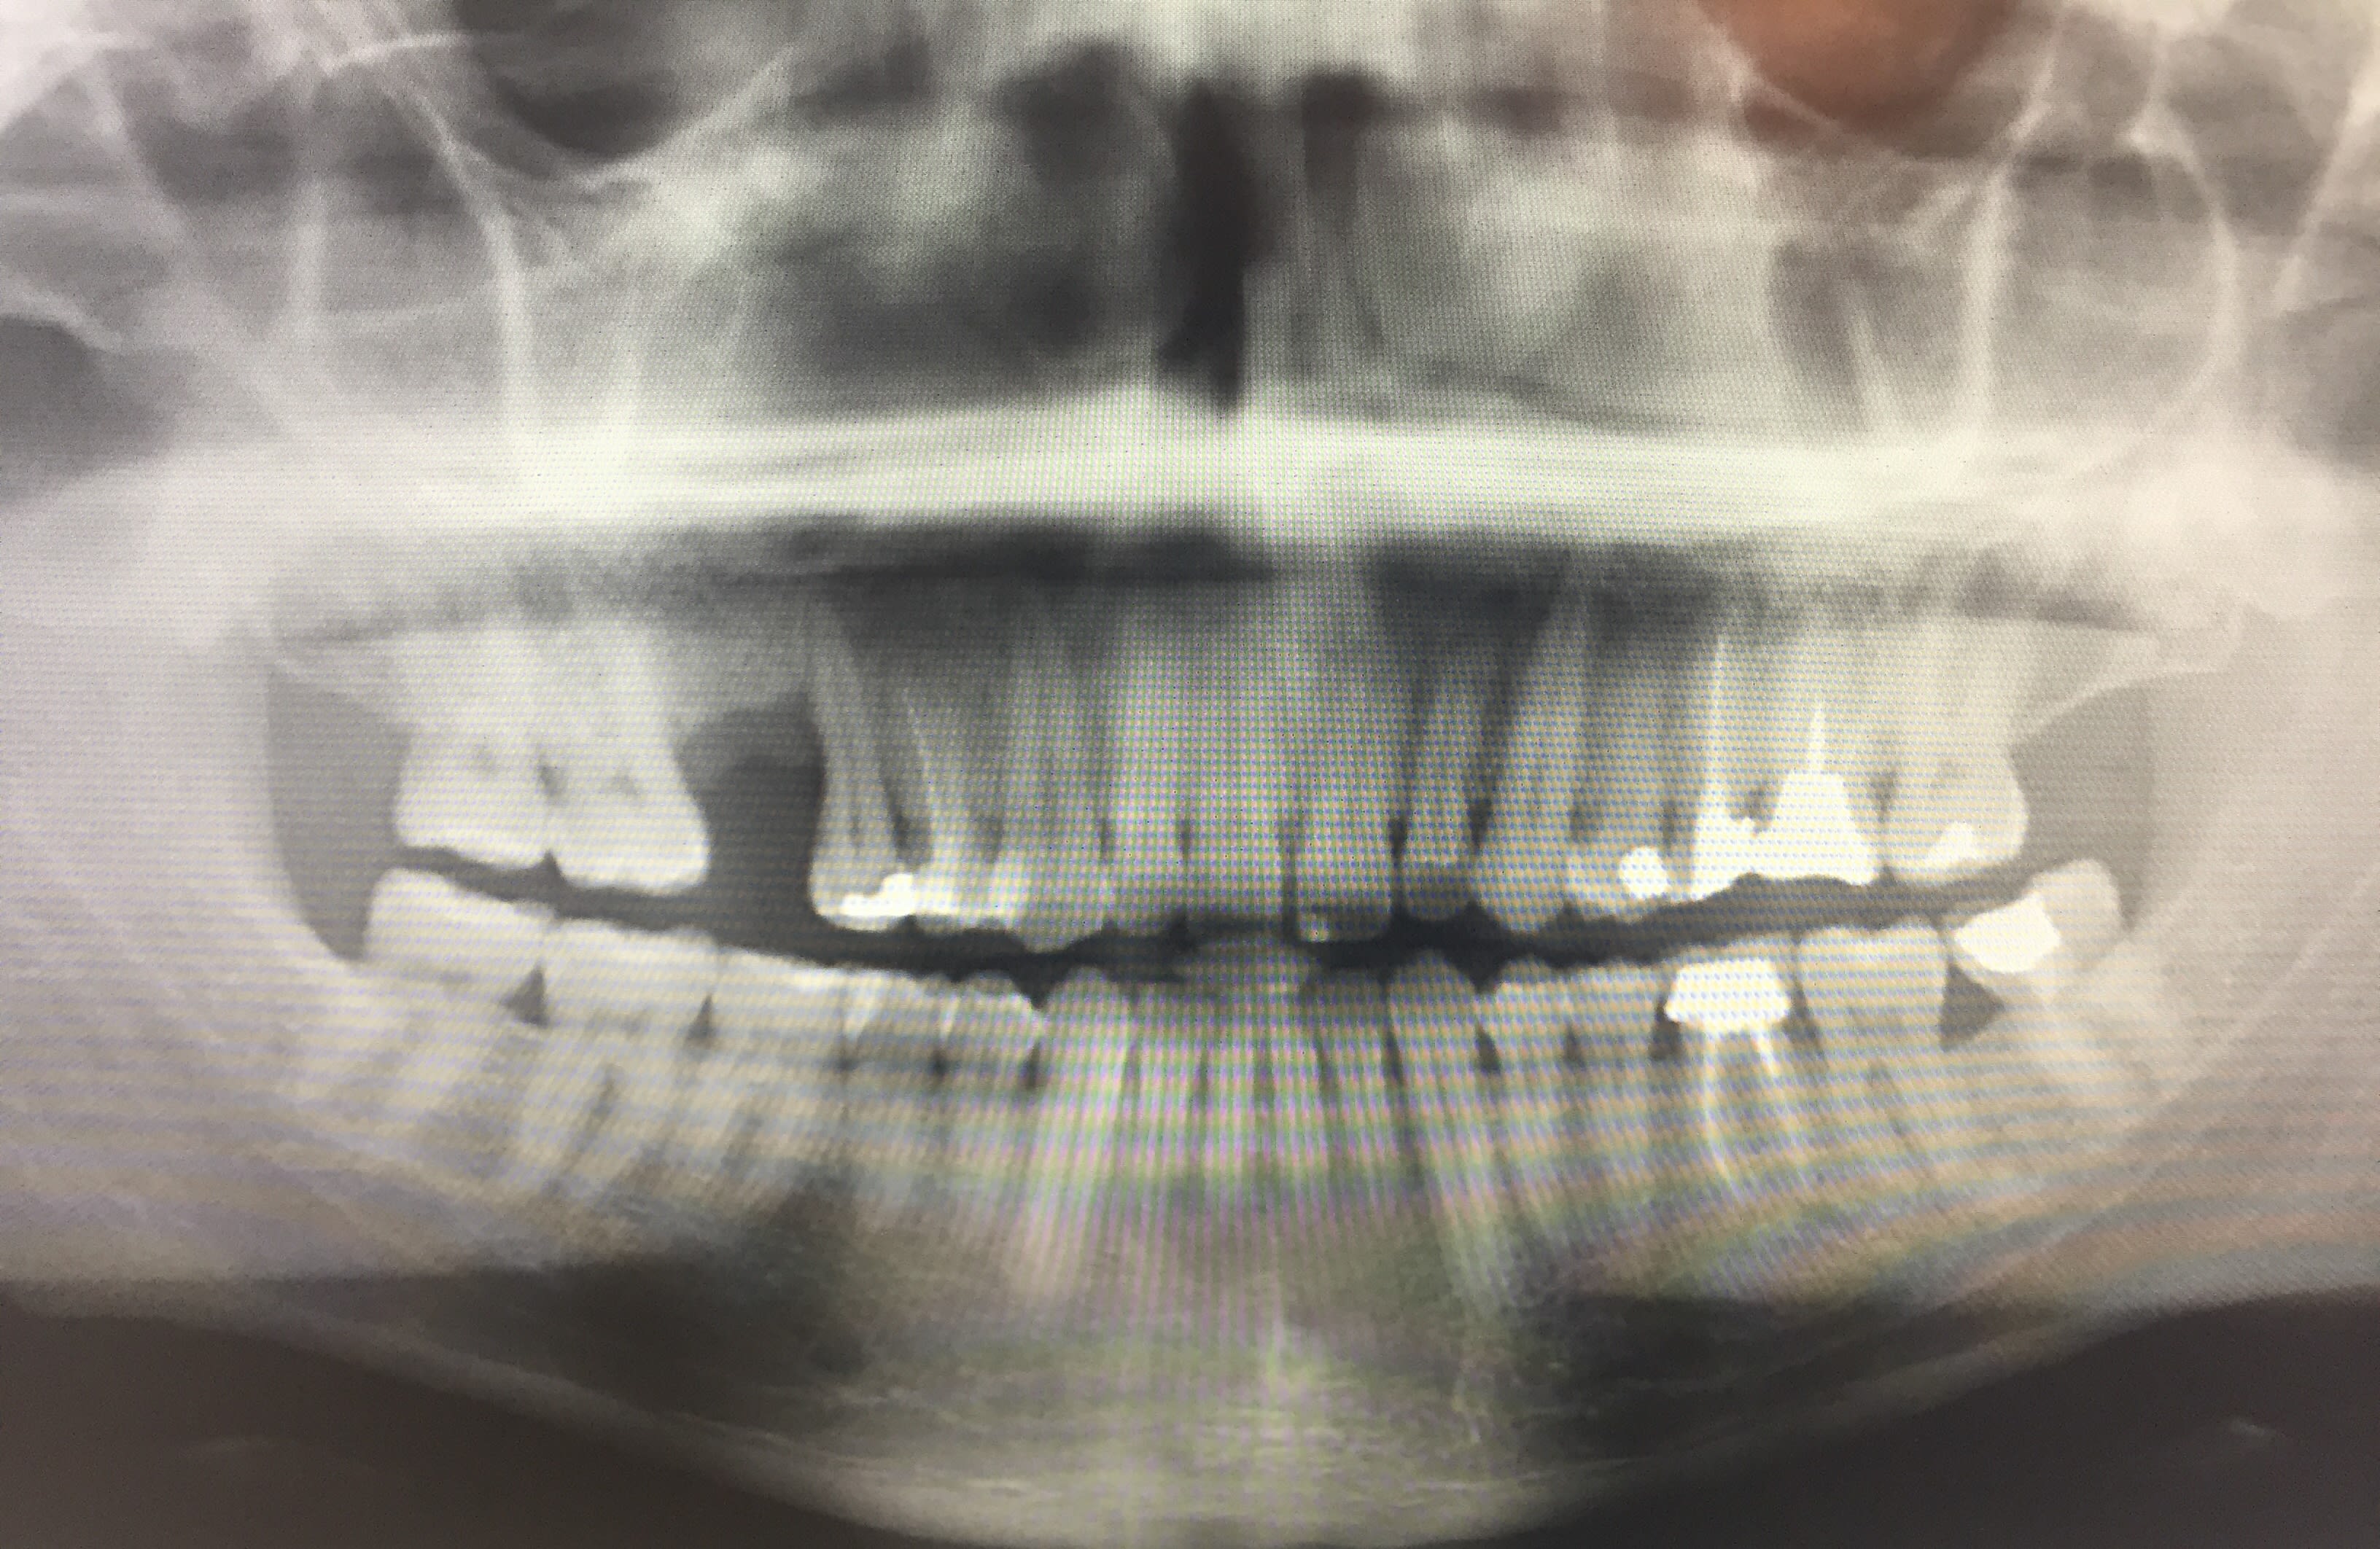

Patient la trentaine bonne santé gé souhaite une solution fixe pour remplacer 16. Bonne hygiène bucco dentaire

15 est légèrement mobile, ne présente pas de poches paro mais récessions de 4-5mm en D, défaut vertical osseux en D.

Que proposeriez vous de prime abord juste en regardant la pano? (cf PJ)

expansion/manipulation latérale pour rattraper la perte osseuse distale sur 15, expansion éventuelle pour l'implant en 16... pas de quoi se prendre la tête avec des prélèvement ramique ... ou autres.

S toutefois 15 ne présente pas de signes autres car l'image pano ne donne pas d'indications suffisante.

Donc si je résume :

(- pourquoi pas proposer 2 couronnes pour 25-26 mais ça n'est pas le plus urgent le patient vient pour son édentement 16)

- solution moins invasive : endo 15 + surfaçage localisée secteur 1 et voir pour combler alvéolyse verticale en D de 15 si possible + par la suite bridge 17-16-15

- solution un peu plus radicale : exo 15 + ROG + implants en 16 et 15

moi je ferais pose d'implant 16 , petite ameloplastie mesiale de 17 , distale de 15 , bon calage de 15 avec la couronne de 16 , bon reglage occlusal et surveillance reguliere de 15 qu'il sera toujours possible de remplacer par un implant .